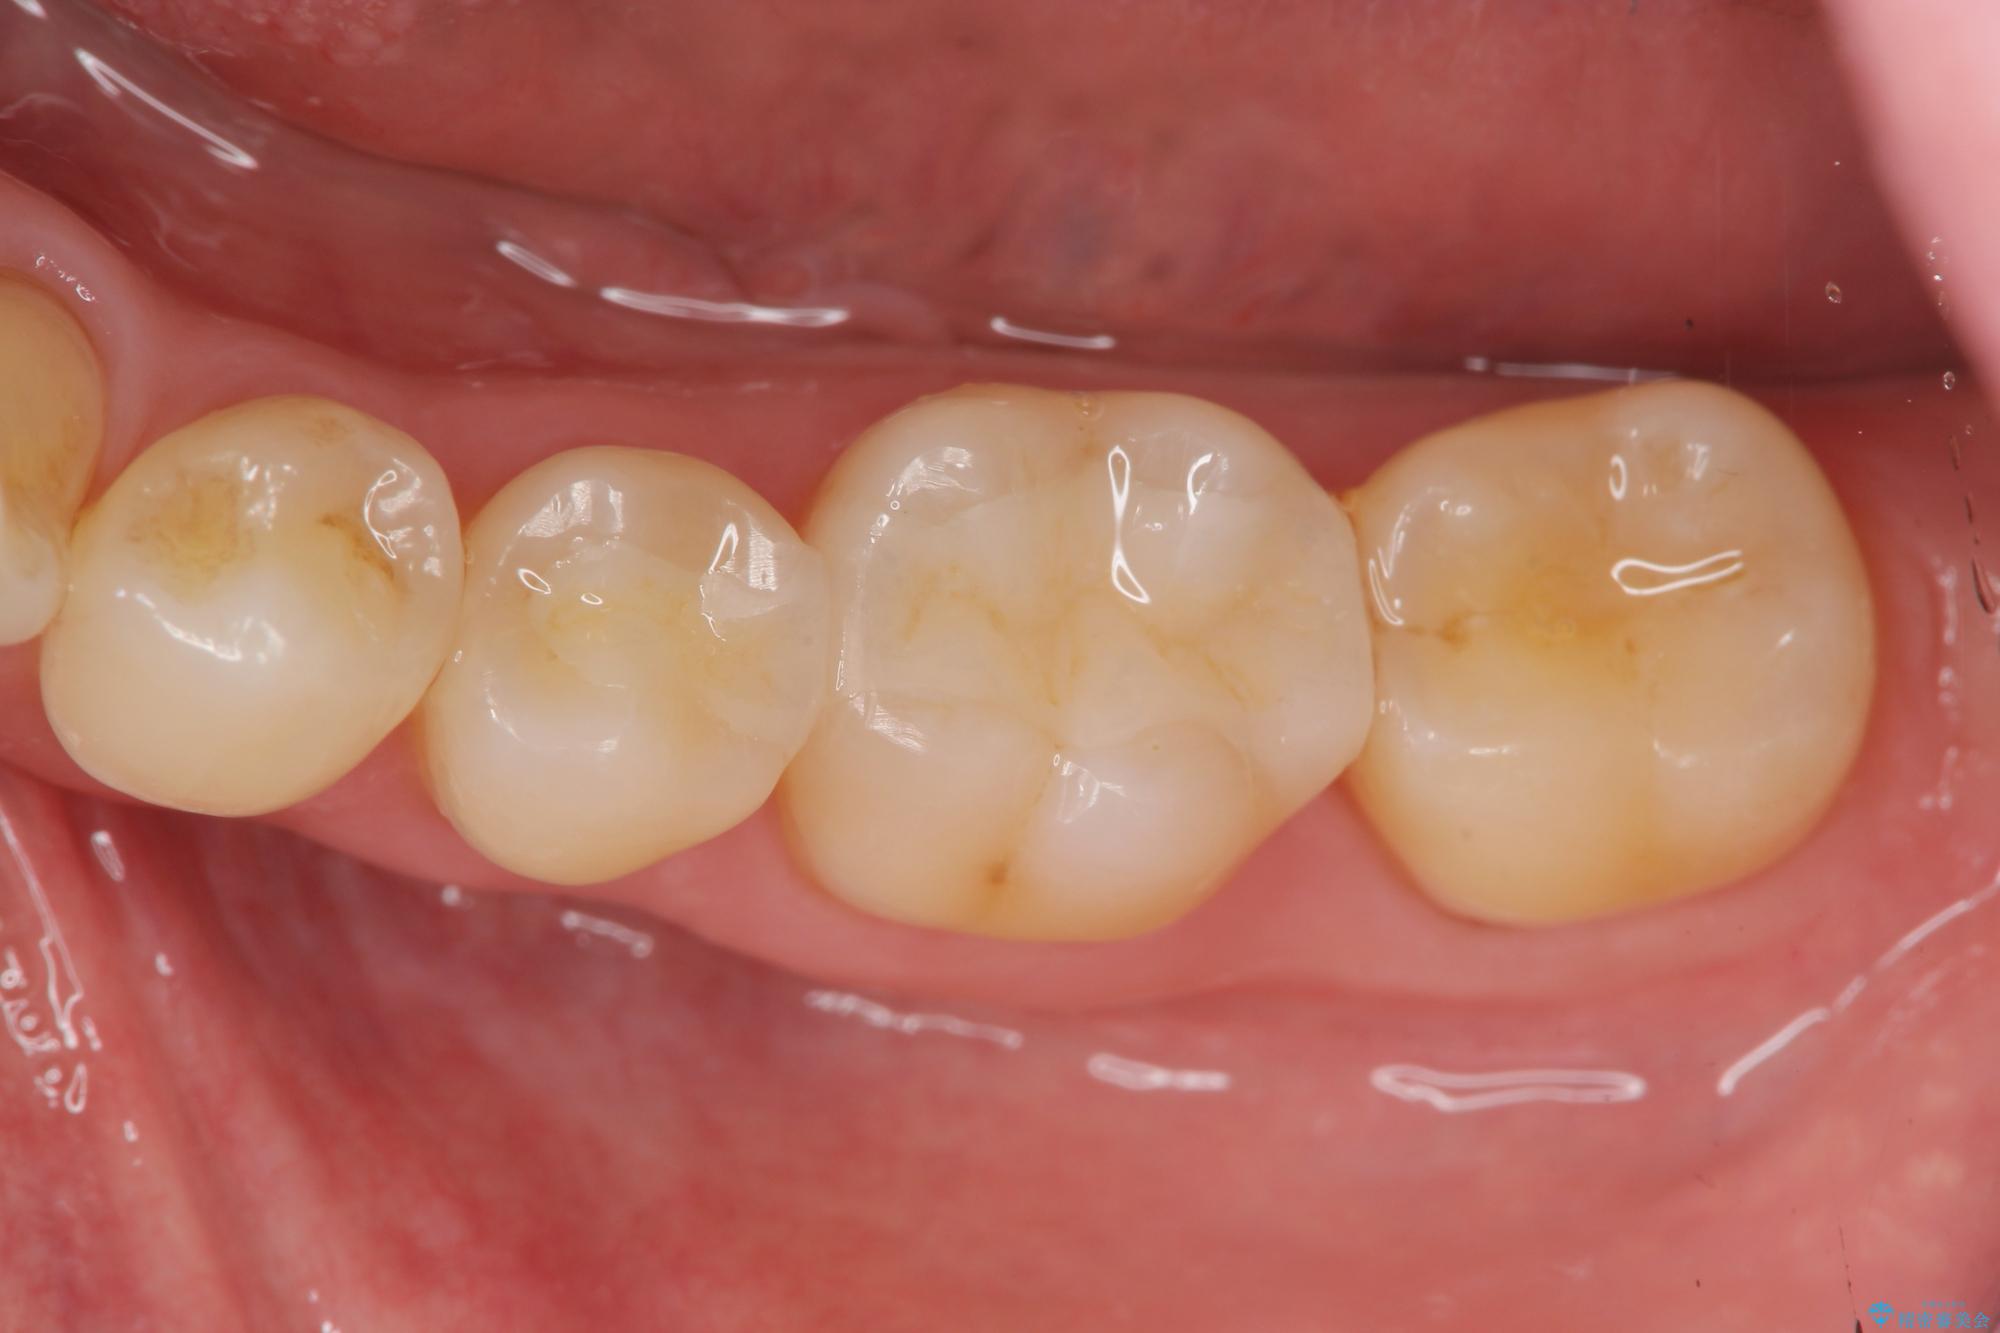

自然なセラミクの仕上がりに満足いただくことができました。

- 15.4万円(セラミックインレー×2)費用は治療当時の料金となります